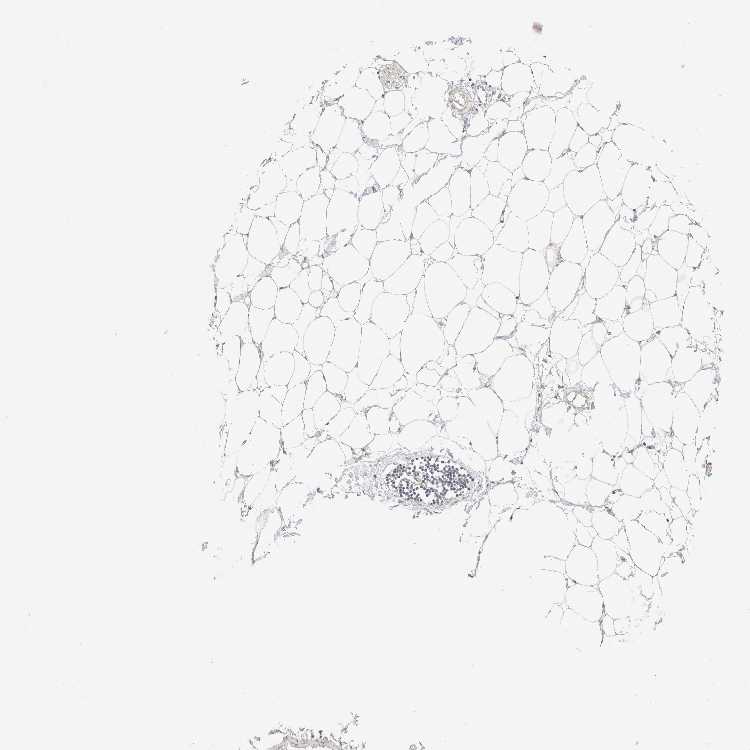

SOFT TISSUE 1 - Antibody stainingi

Antibody staining in the annotated cell types in the current human tissue is reported as not detected, low, medium, or high, based on conventional immunohistochemistry profiling in selected tissues. This score is based on the combination of the staining intensity and fraction of stained cells.

Each image is clickable and will lead to virtual microscopy that enables deeper exploration of all samples and also displays staining intensity scores, fraction scores and subcellular localization as well as patient and tissue information for each sample.

Antibody HPA024659

Fibroblasts Not detected

Peripheral nerve Medium